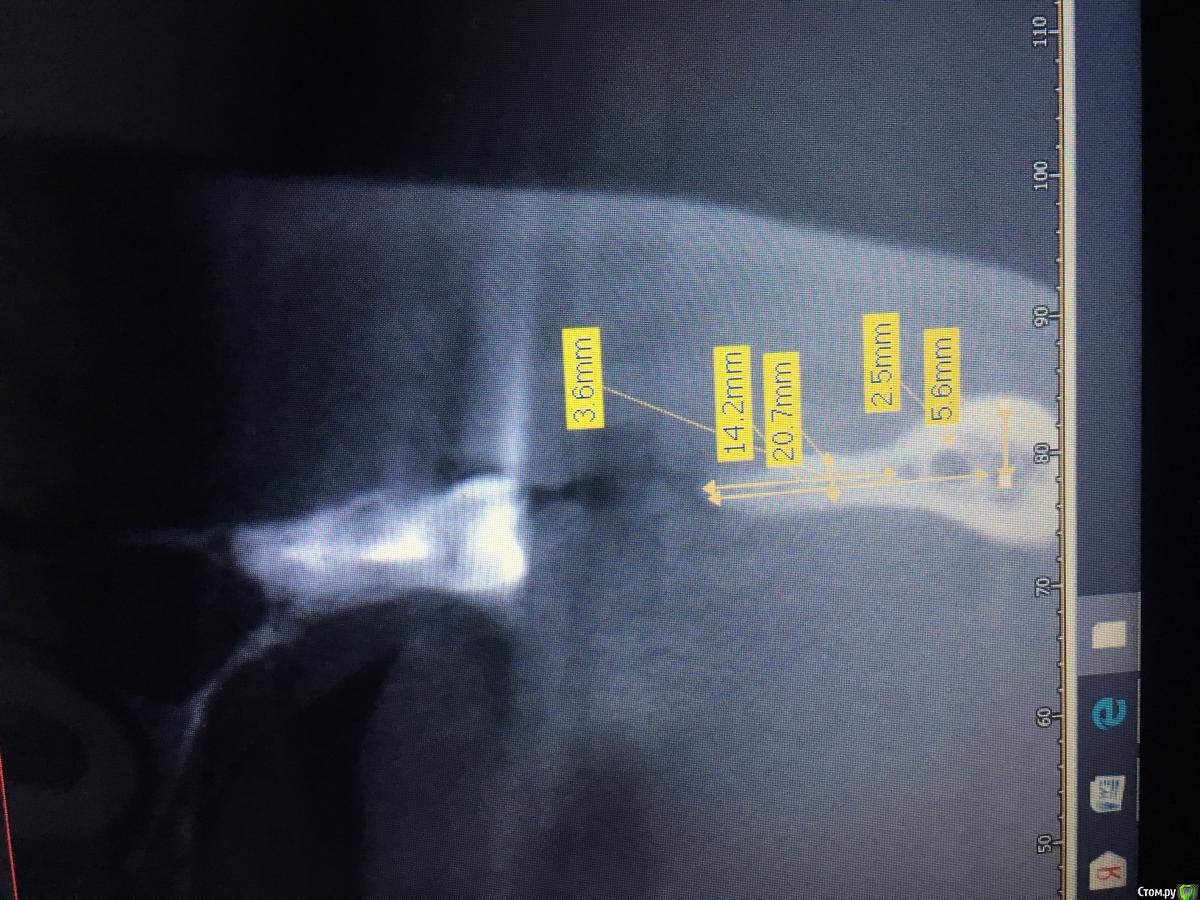

Drbelyshev Опубликовано 30 июля, 2019 Поделиться Опубликовано 30 июля, 2019 Костная пластика. Работает ли osteoplant flex в данном случае? Ссылка на комментарий

АнтонТЛТ Опубликовано 30 июля, 2019 Поделиться Опубликовано 30 июля, 2019 Судя по снимкам, нужно язычно аугментировать. И данный материал не особо подходит. Тут выбор в пользу хорошо набитой сосиски, либо что-то более жесткое (сетка, ламинаты по Кури или армированные мембраны). 4 Ссылка на комментарий